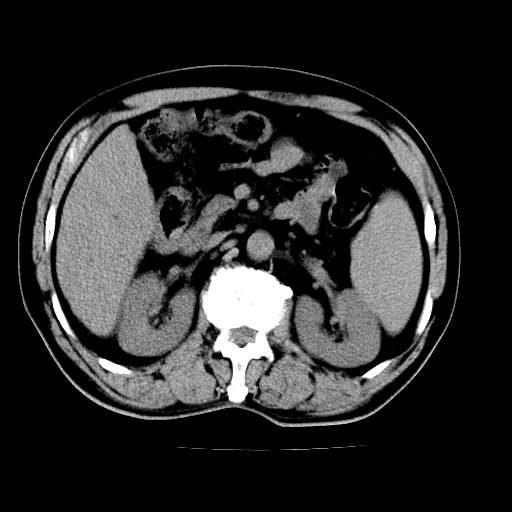

男,66岁,上腹部不适、黄染一周。彩超示:肝左叶占位,肝内胆管扩张,胆总管扩张,胆总管占位?

肝左叶占位性病变,并胆管扩张,符合胆管细胞癌ct表现,门脉左支受累,左肾囊肿。窗宽太窄了,其他的看不清

左叶胆管细胞癌累及胆总管,门脉左支受侵,慢性胆囊炎胆结石,左肾小囊肿

支持 1肝左叶肝内胆管细胞癌伴胆总管及门脉左支受侵。2胆囊钙乳症。

支持 1)肝左叶胆管细胞癌伴胆总管及门脉左支受侵。2)胆囊钙乳症。